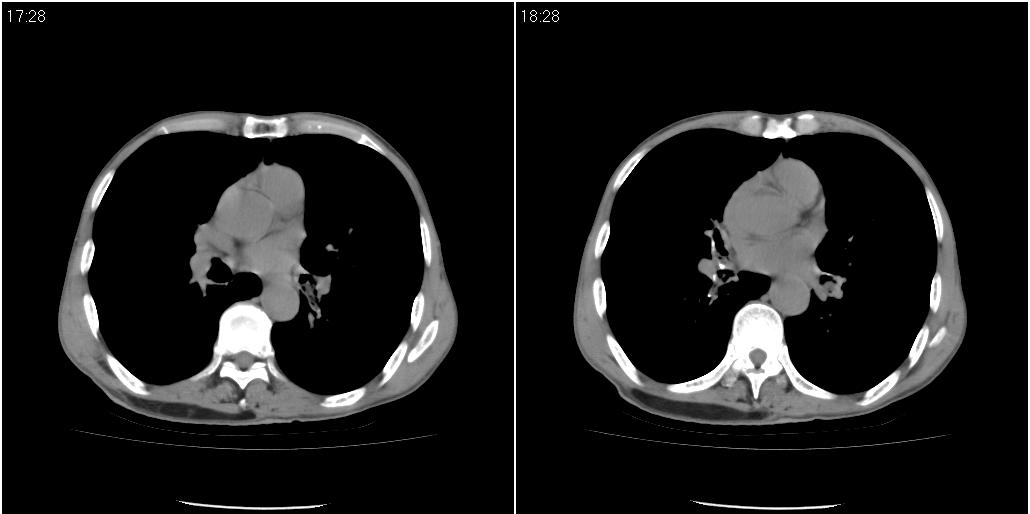

标题: CT25416:男性,70岁。胸片发现右下肺斑片状阴影 [打印本页]

标题: CT25416:男性,70岁。胸片发现右下肺斑片状阴影

以下是ct检查的情况:

考虑右肺下叶炎症可能性大?未除占位,建议增强。右下肺肺不张

右下胸壁皮下气肿。

炎症?占位建议纤支镜或增强检查

右下肺阻塞性肺炎!建议纤支镜!